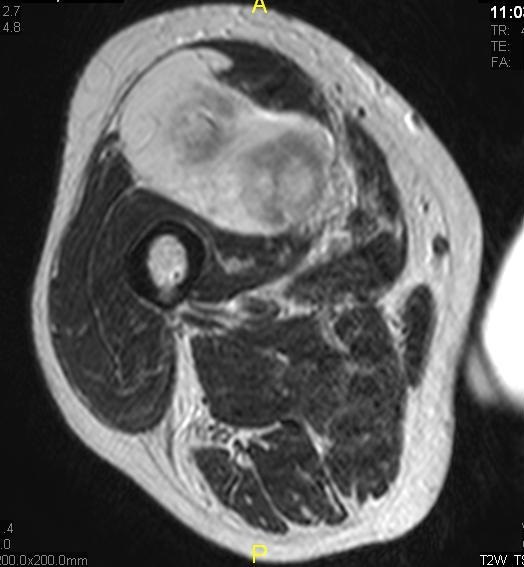

Fig. 1 & 2 Magnetic Resonance Image shows a large heterogeneous mass in the left gluteal region with low intensity signal on Axial (Fig. 1) and Coronal (Fig. 2) T1-weighted images admixed with some high signal areas indicative of fatty tissue. Higher intensity signal is visible compatible with hemorrhage or necrotic tissue. The mass involve the central portion of the left iliac bone.

Fig. 3 Axial fat suppressed T2-weighted MR image demonstrates a large heterogeneous mass with multiple thick internal trabeculations. Fatty areas suppress on T2 weighted fat suppressed areas